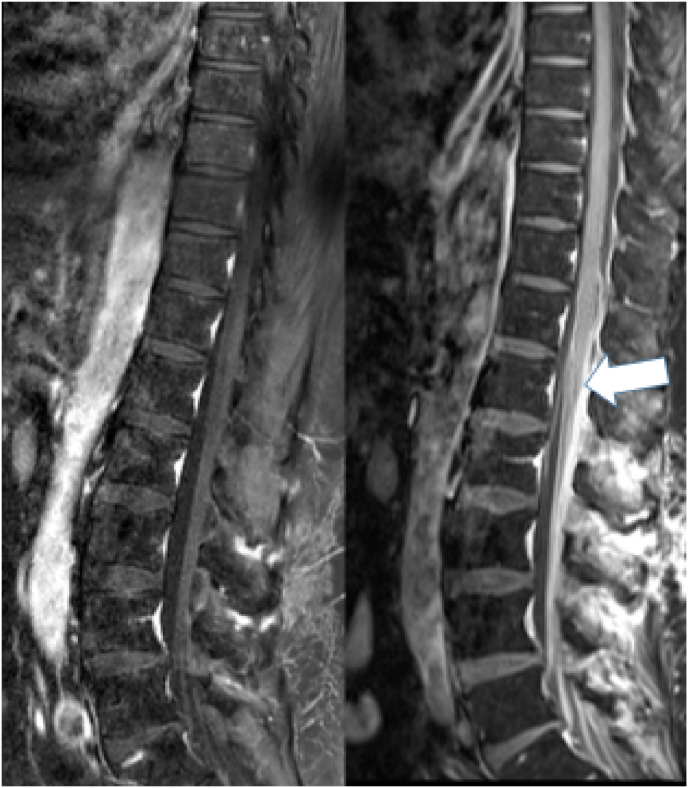

Material and methods: In this paper we report the case of a 53-year-old man who was, in the course of his treatment for acute lymphoblastic leukemia (ALL), inadvertently injected with vindesine intrathecally. The patient survived following aggressive and invasive treatment, which included irrigation of the CSF via external ventricular and lumbar drains. We also conducted a systematic review of similar published cases.

Result: A total of 31 cases with intrathecal inadvertent vinca alkaloid injection were identified. Including the case described in this report only two patients were injected with vindesine (n = 2, 6.5 %), all other received vincristine. Only 6/31 (19.4 %) patients survived the acute phase of the vinca alkaloid intoxication. 6/15 (40.0 %) patients receiving some sort of CSF irrigation survived (cf. 0/12 without irrigation therapy). All survivors were left with very significant neurological deficits.

Discussion and conclusion: The combined evidence suggests that intrathecal administration of vincristine is universally fatal without treatment, while CSF irrigation carries a chance of survival. Patients are, however, left with severe neurological deficits such as paraplegia.